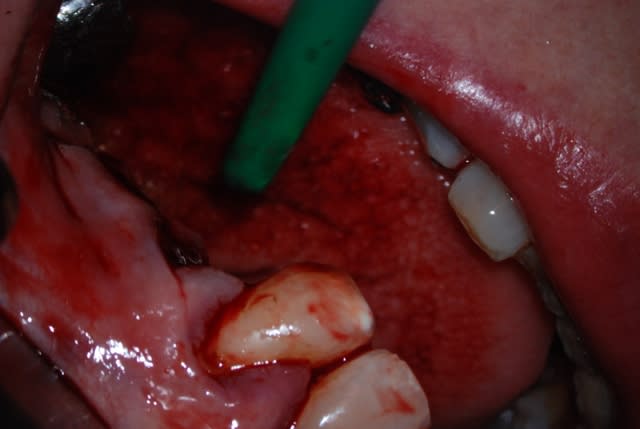

Comme tu as fait un super boulot en endo, autant faire le max en paro maintenant. Il conviendrait de saquer la 48 mésioversée et lors de cette chir décoller un peu en antérieur, surfacer la racine distale et la zone inter radiculaire de la 46. Pas de matériau de comblement car il n'y a plus de paroi osseuse pour le soutenir.

c'est exactement mon intention:)

tu crois? je comptais en mettre:en Mesial il reste la paroi osseuse

Comment fais-tu pour que ça saigne aussi peu sur ton intervention?

Un produit miracle?

La seule anesthésie?

Aucun produit. Je ne suis pas un adepte du sulfate ferrique. J'ai egalement essaye l'argile verte, mais trop dur de refaire saigner en fin d'interventin.

Je place des petits morceaux de compresses imprégnés de Rentensorb ( le produit des tampax) les unes sur les autres.

Une anesthesie sous periostée est effectivement nécessaire.